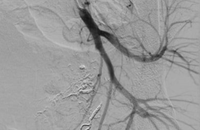

Hình ảnh dị vật kẹt trong tim bệnh nhân (Ảnh - BVCC) |

Đến tháng 11/2021, sau 6 năm, dây nối của buồng truyền bị đứt, trôi theo mạch máu và bị kẹt lại trong tim của bà H. Tại Bệnh viện Hữu nghị Việt Đức, các bác sĩ đã can thiệp lấy dị vật cho bệnh nhân.

ThS.BS. Thân Văn Sỹ - Khoa Chẩn đoán Hình ảnh, Bệnh viện Hữu nghị Việt Đức - cho biết: Các bác sĩ đã sử dụng dụng cụ can thiệp đưa vào buồng tim và lấy dị vật ra ngoài cho bệnh nhân chỉ trong vài phút. Quá trình can thiệp nhanh chóng và nhẹ nhàng đến nỗi người bệnh phải thốt lên trong ngỡ ngàng, khi ôm nỗi sợ phẫu thuật suốt 6 năm, không dám vào viện để lấy buồng truyền ra cho tới khi xảy ra biến chứng nguy hiểm. Sau can thiệp, bệnh nhân ổn định, dự kiến sẽ được xuất viện trong 1-2 ngày.